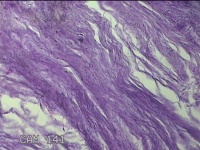

右拇指远端结节

性别

男

年龄

37岁

临床诊断

皮脂腺囊肿

一般病史

发现右拇指远端结节2年余。

标本名称

大体所见

灰白粉红色组织1.8x1.2x00.8cm一个,表面带梭形皮肤1.3x0.7cm,皮下见结节1.2x0.8cm一个,切开结节呈实性,切面灰白粉红色,质中。

图2